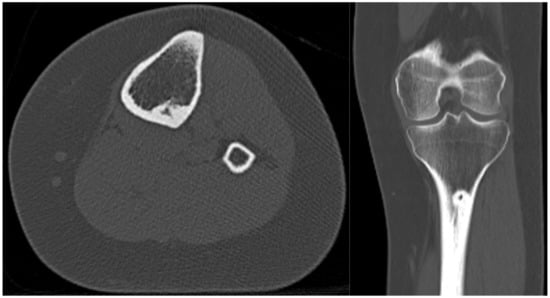

3. Case 2